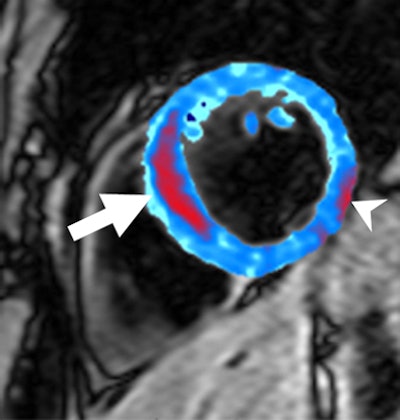

| Image of a left anterior descending artery occlusion acquired by T2-weighted MRI prior to contrast administration. Red area shows a region of postreperfusion hemorrhage (arrow). Susceptibility artifact adjacent to inferolateral epicardium was manually excluded (arrowhead). Image courtesy of the Medical Research Council Clinical Sciences Centre in London and Radiology. |

"Transmural edema was present in all subjects on the T2-weighted short inversion time inversion recovery images and was in the same anatomic region as the late gadolinium enhancement," the authors wrote.

The mean area of hemorrhage, as indicated by a T2 measurement of less than 20 msec, was 5% at the level of the infarct. The researchers set the 5% value of the hemorrhage area as the cutoff value for subsequent subgroup analysis. Six of the 15 patients demonstrated 5% or more hemorrhage after reperfusion.